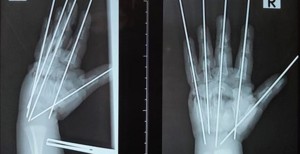

«Ребёнка доставили в клинику Педиатрического университета в 4:15 утра — сразу в операционную, минуя приёмный покой. В ходе операции специалисты Педиатрического университета буквально собрали по частям травмированную руку мальчика», — рассказали в сообществе.

Ребёнку потребовалась аутовенозная пластика: размозженный участок локтевой артерии хирурги заместили фрагментом подкожной вены пациента. Медики отметили, что после этого пальцы ребёнка стали понемногу розоветь.

Операция продлилась более пяти часов. Сейчас пациент находится в отделении реанимации.